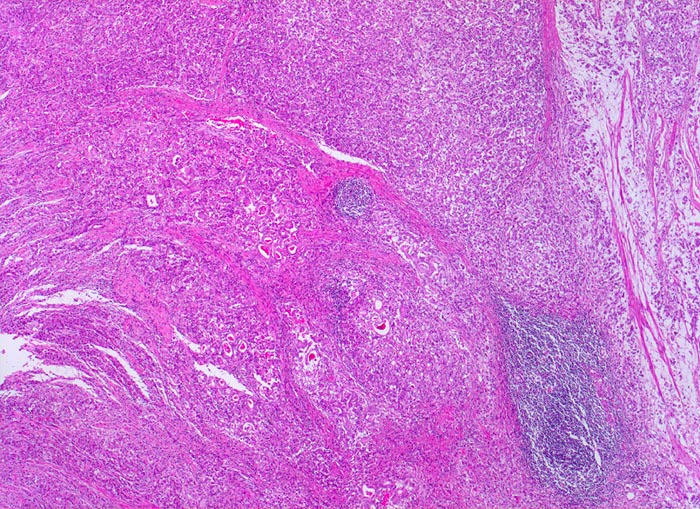

• Das unscharf begrenzte Karzinom breitet sich diffus in der gesamten Magenwand und in der Ösophaguswand aus bis in des periösophageale und subseröse Fettgewebe.

• Ein Grossteil des Tumorinfiltrats besteht aus einzeln oder in kleinen Gruppen liegenden Zellen mit intrazytoplasmatischen Schleimvakuolen, die teilweise den Kern verdrängen (Siegelringzellen): diffuser Typ des Magenkarzinoms nach Lauren.

• Lymphgefässeinbrüche.